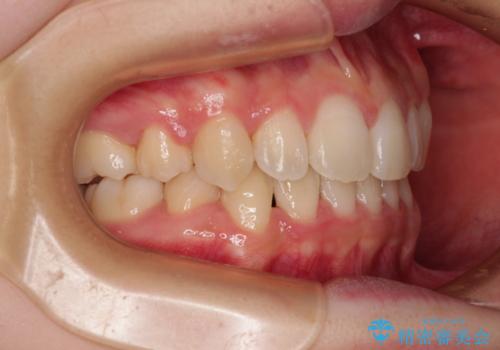

- 口元の閉じにくさを気にして来院された患者様です。

上下ともに歯列が前方に突出していたため、上下左右の第一小臼歯4本を抜去し、ワイヤー装置による矯正治療を行うこととしました。

舌の突出癖による影響もあったため、舌のトレーニングを並行して実施しました。